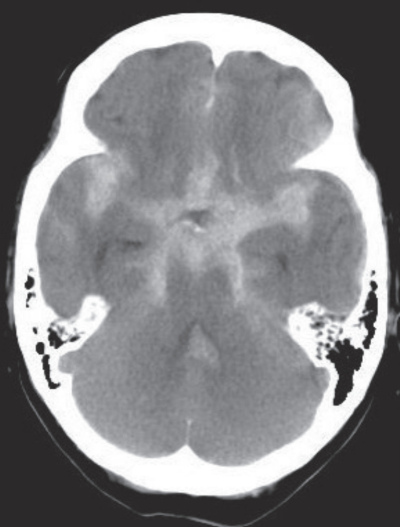

初診時に撮影した頭部単純CTを別に示す。入院後、ICUに入室して保存療法で経過を観察した。翌日の所見は以下のとおりであった。